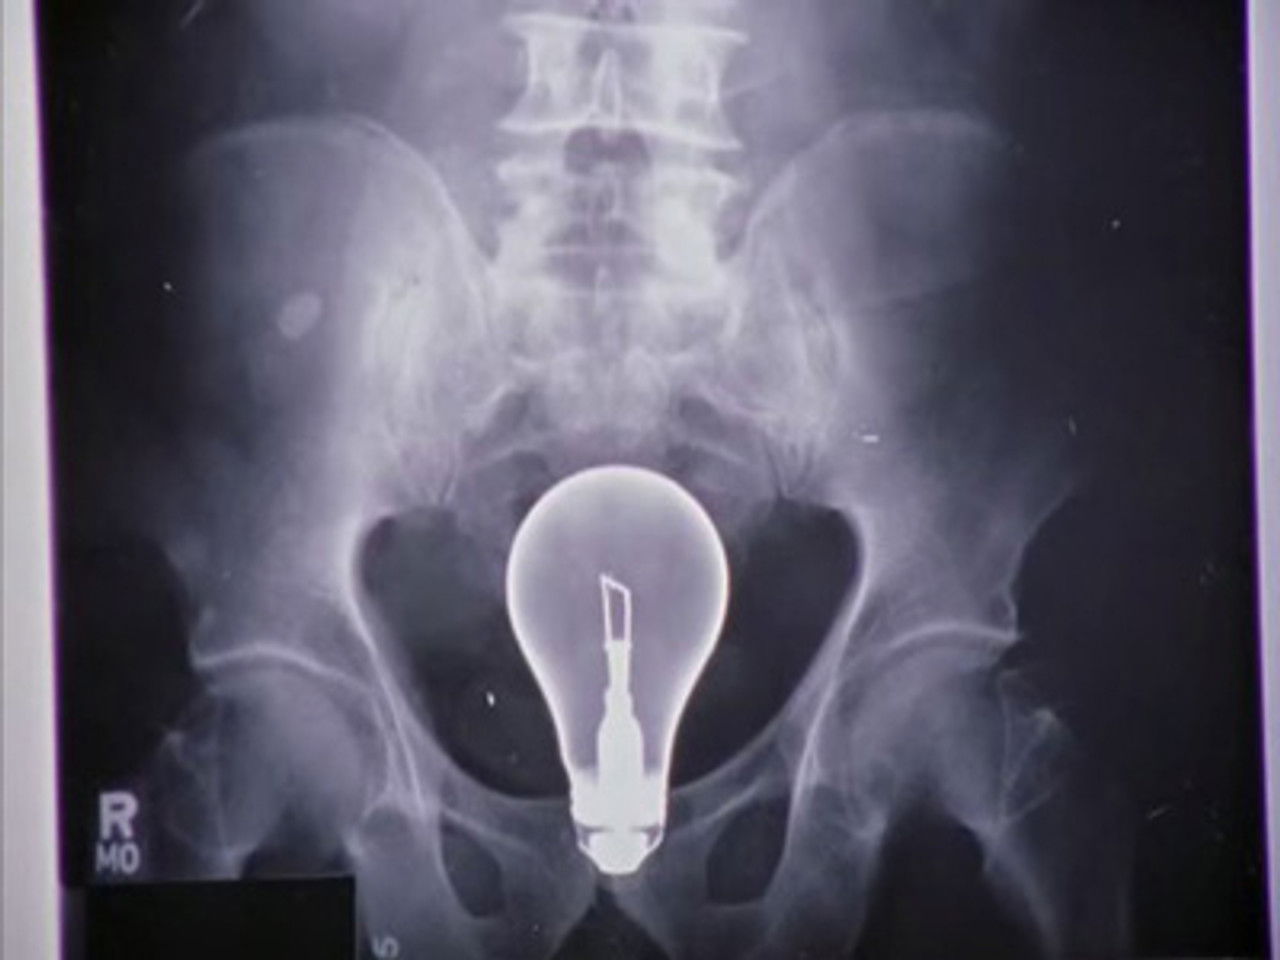

Molly travaille sur la résolution des conflits en milieu hospitalier et choisit le docteur Cox comme sujet d'étude. Pourvue de bonnes intentions, elle tente de réconcilier JD et Elliot, en compétition pour décrocher le poste de Chef des internes. Pendant ce temps, Cox, JD et le concierge essaient de résoudre le mystère de l'hôpital : comment extraire une ampoule du ventre d'un patient sans la briser ?